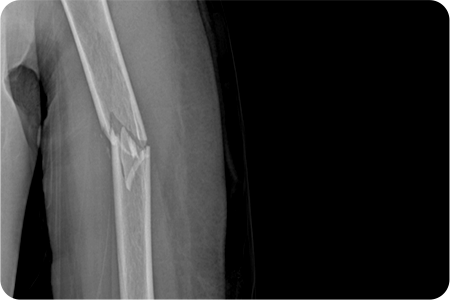

• 위팔 골절, 쇄골 골절, 손목 골절은 손을 짚으면서 넘어질 때,

팔을 곧게 뻗은 채로 넘어질 때나, 교통사고, 타박 등에 의해 발생합니다.

골다공증 등으로 인해 뼈가 약해진 분에게 더 쉽게 발생할 수 있습니다.

• 골절이 발생한 부위 주변으로 통증과 압통이 발생하는데,

이 통증은 근육의 경직, 뼛조각의 겹침, 주위 연부 조직의 손상이 원인입니다.

골절 부위가 붓고, 피부 바깥에 보이는 점상 출혈이 발생합니다.

• 골절이 조금이라도 의심된다면 반드시 X-ray 촬영을 시행하여 확인해야 합니다.

부위별로 방향과 각도를 달리하여 여러 장의 X-ray를 찍어서 골절 유무를 확인합니다.

상완골 골절 수술

X-ray 및 CT를 통해 골절 형태와 전위 정도를 확인합니다.

골절된 뼈를 원래 위치로 맞추는 정복 작업을 진행합니다.

금속판, 나사, 고정막을 이용해 뼈를 고정합니다.